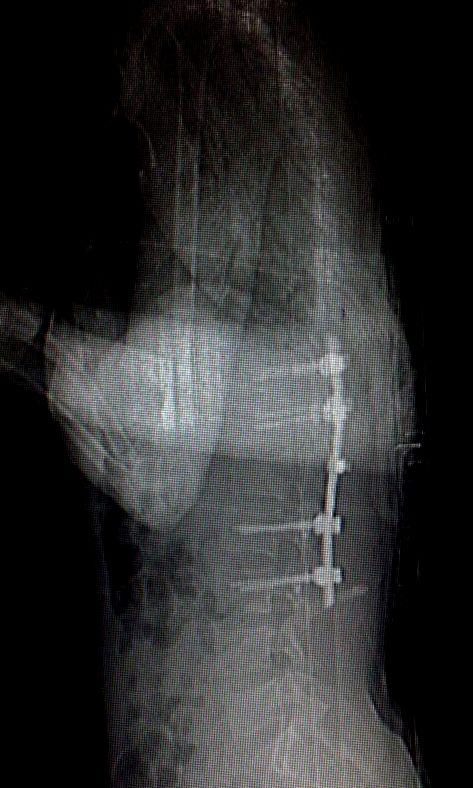

REBORN POSTERIOR CERVICAL SYSTEM

Posterior Cervical Fixation System Posterior Cervical Stabilization System (Screws-Rod-Connectors); this...